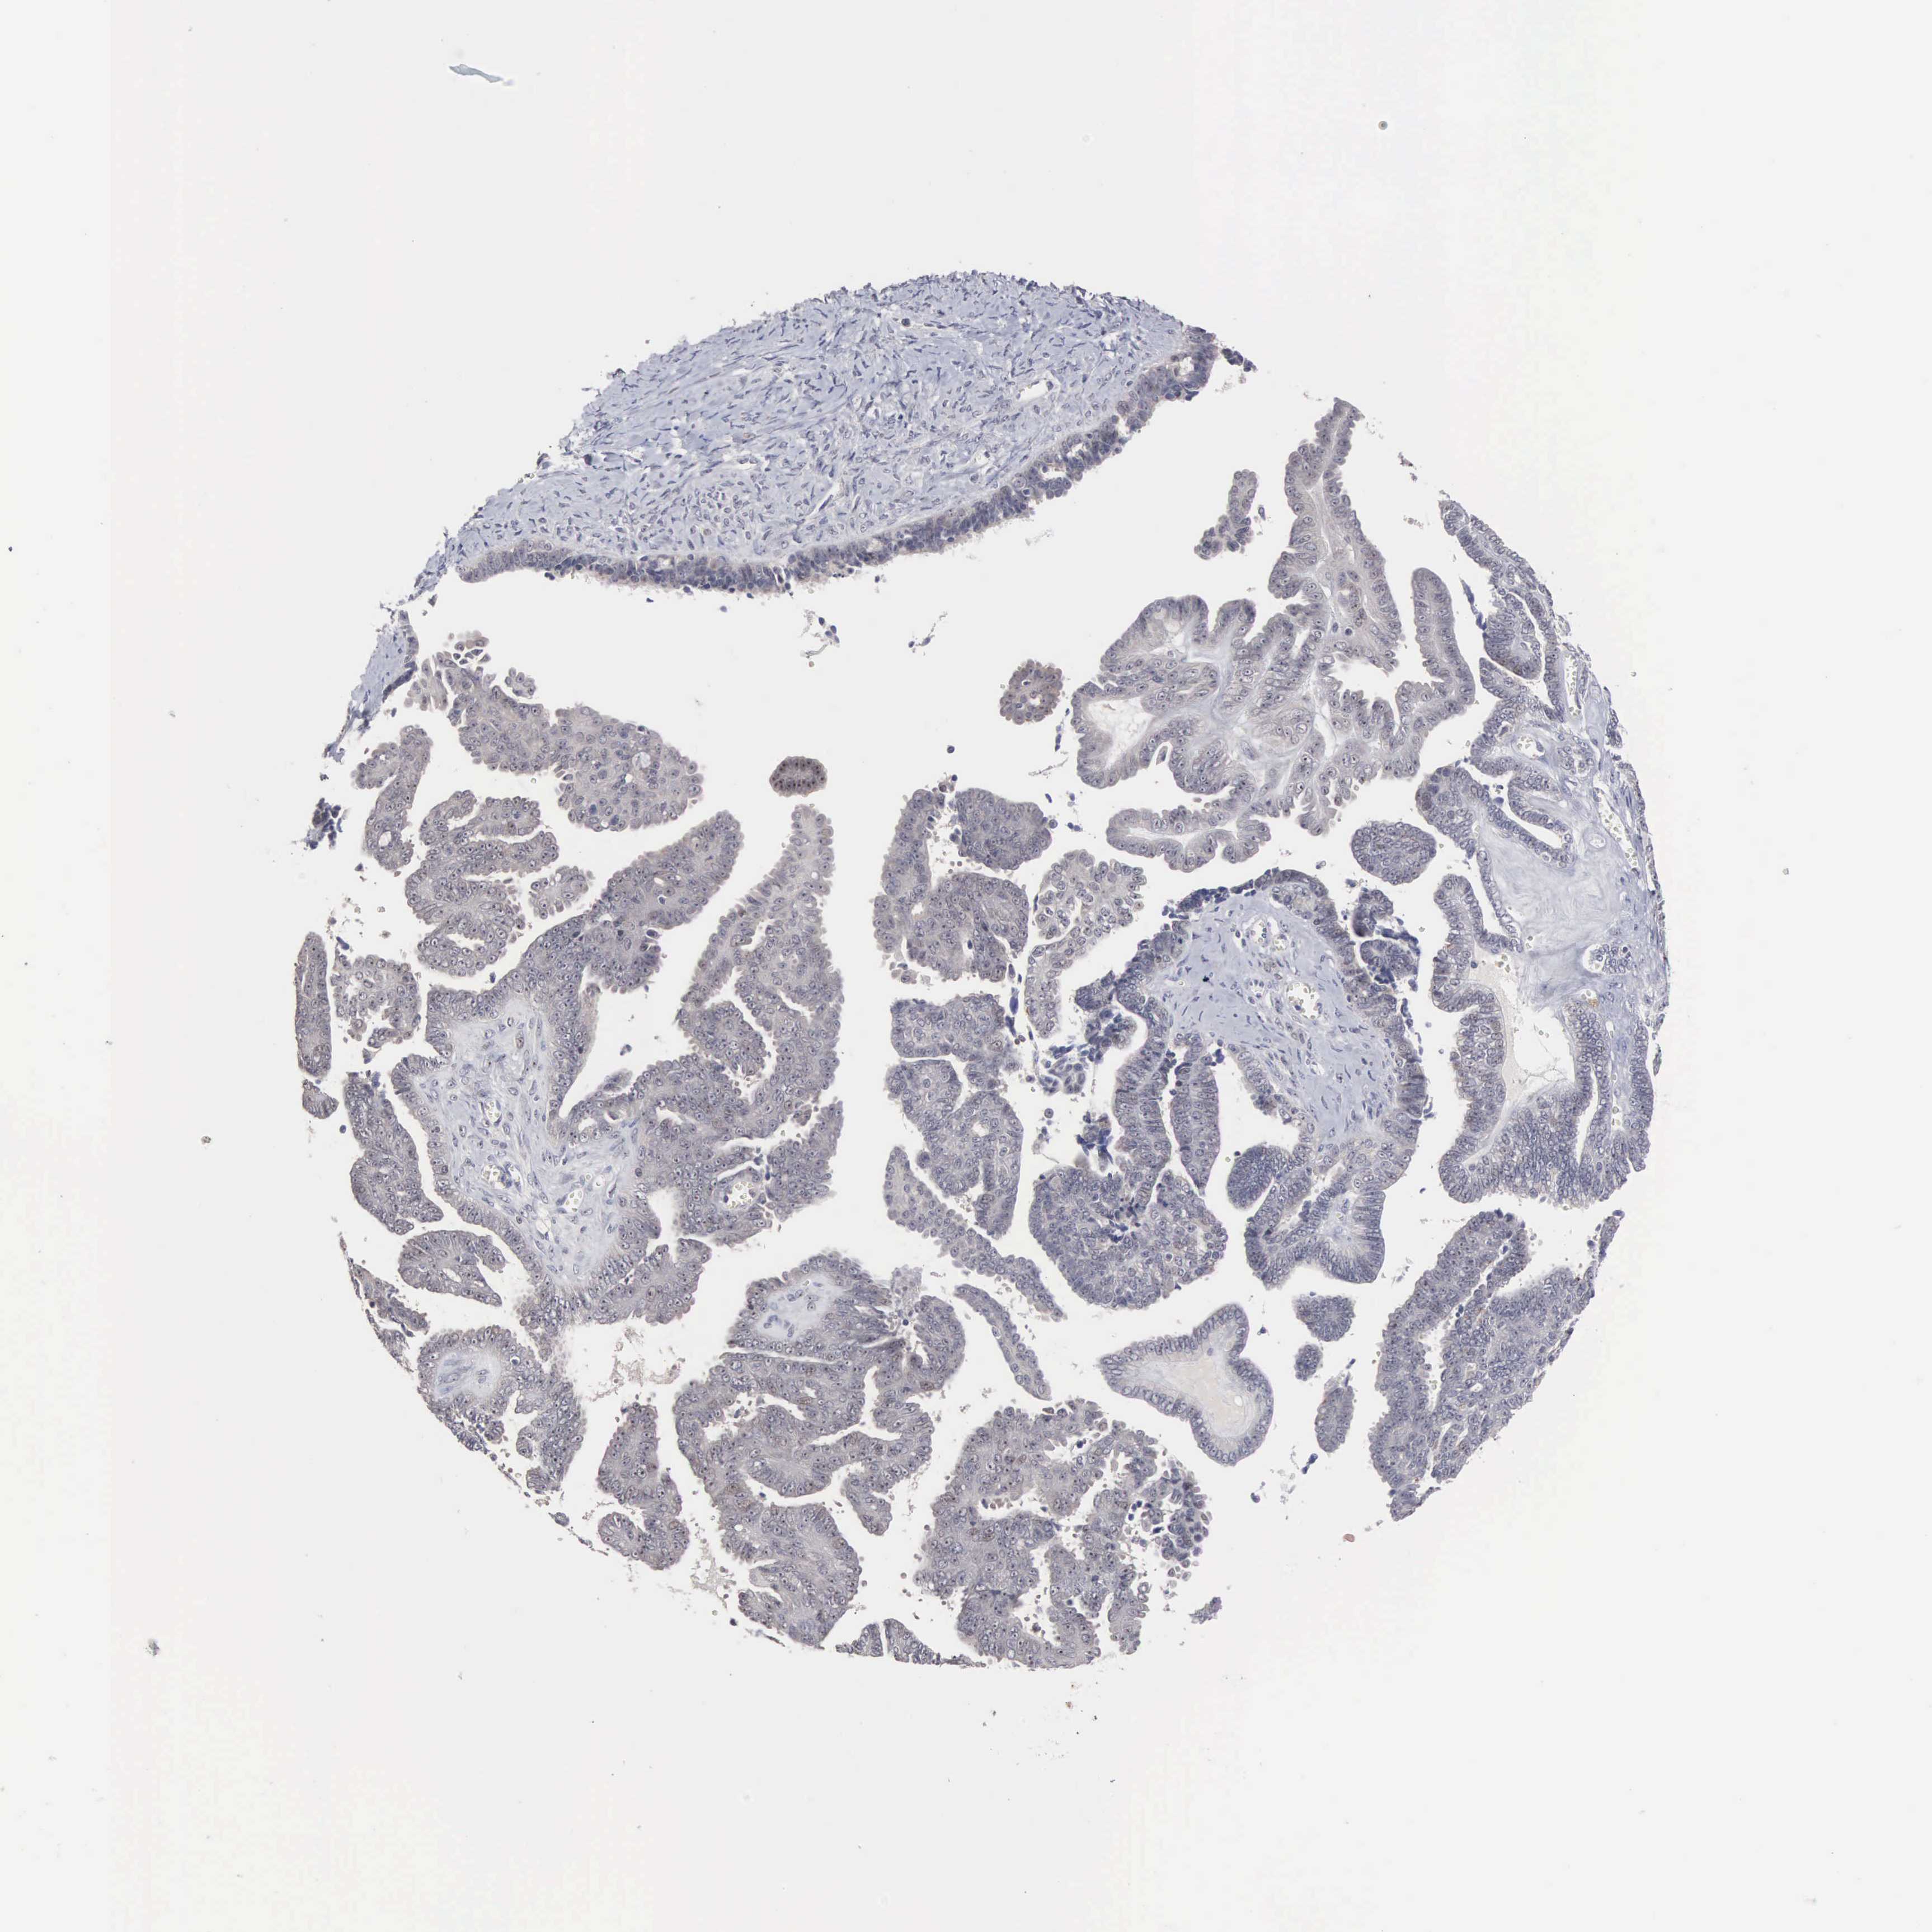

OVARIAN CANCER - Protein expressioni

A mouse-over function shows sample information and annotation data. Click on an image to view it in a full screen mode. Samples can be filtered based on level of antibody staining by selecting one or several of the following categories: high, medium, low and not detected. The assay and annotation is described here.

Note that samples used for immunohistochemistry by the Human Protein Atlas do not correspond to samples in the TCGA dataset.

Antibody stainingi

Antibody staining in the annotated cell types in the current human tissue is reported as not detected, low, medium, or high, based on conventional immunohistochemistry profiling in selected tissues. This score is based on the combination of the staining intensity and fraction of stained cells.

Each image is clickable and will lead to virtual microscopy that enables deeper exploration of all samples and also displays staining intensity scores, fraction scores and subcellular localization as well as patient and tissue information for each sample.

Antibody HPA000779

Staining

High

Medium

Low

Not detected

Intensity

Strong

Moderate

Weak

Negative

Quantity

>75%

75%-25%

<25%

None

Location

Nuclear

Cytoplasmic/membranous

Cytoplasmic/membranous,nuclear

Cystadenocarcinoma, mucinous, NOS

Carcinoma, endometroid

Cystadenocarcinoma, serous, NOS